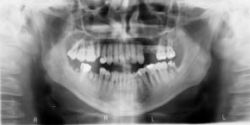

Krvné doštičky v službách stomatológie Liečba ochorení

Krvné doštičky v službách stomatológie

Plne funkčný a anatomický vyhovujúci chrup je významným faktorom z hľadiska výživy organizmu, spoločenského a životného uplatnenia. Zlý stav chrupu našej populácie súvisí aj s rôznymi ochoreniami, ktoré spôsobujú nedostatok kostného tkaniva.